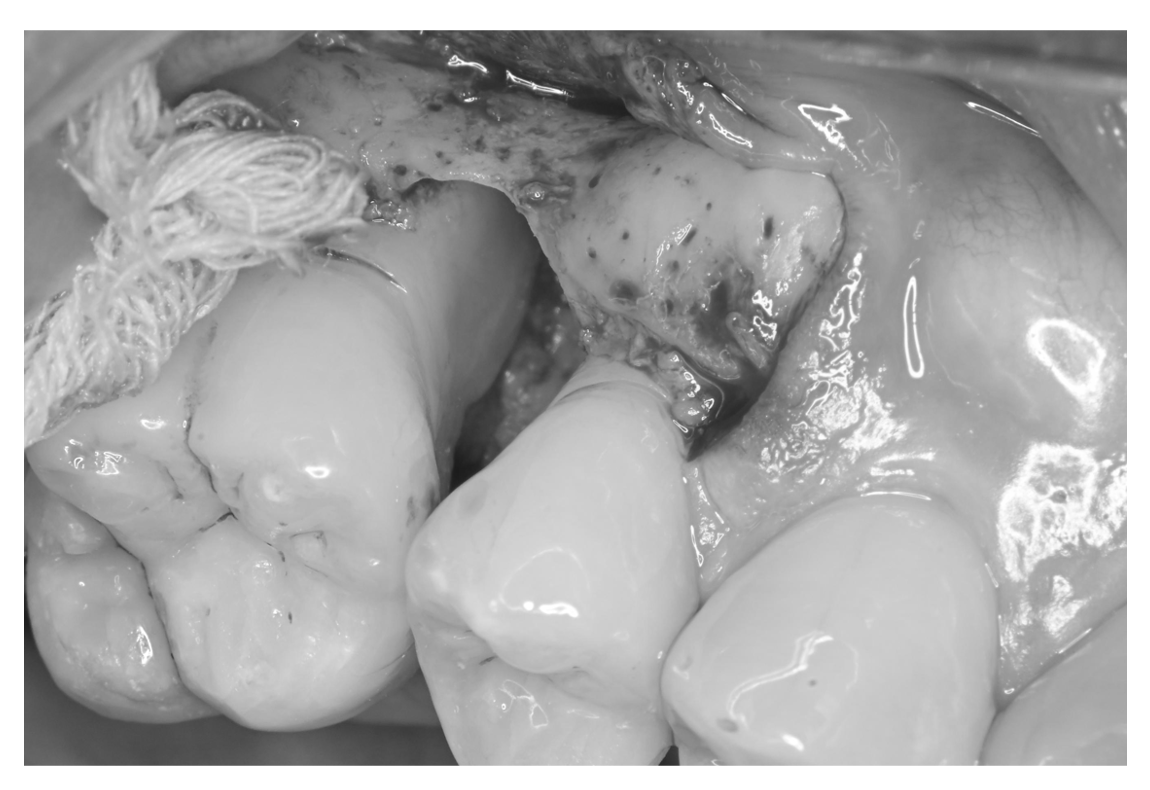

歯周病で歯を支える歯が溶ける?

歯周外科時(スケーリング・ルートプレーニング後)

| 主訴 | 歯科医院に定期的に通っているが、深い歯周ポケットが残存しているのでかかりつけ医より当院を紹介されて来院。定期的に歯茎が腫れるとのこと。 |

| 治療内容 | 歯周基本治療終了後に歯周組織再生療法を実施 ポケット8mmを超える部位では大きな骨欠損を認める。この原因は『歯石』、つまりは細菌の塊がその場所にいたことで歯を支える骨が溶けてしまったのです。 |

| 治療期間 | 9ヶ月 歯周基本治療(2ヶ月) 歯周外科治療、歯周組織再生療法(1ヶ月) 歯周組織再生療法後は6ヶ月経過を確認しメインテナンスへ |

| 費用 | 歯周組織再生療法(サイトカイン+骨補填剤の併用療法) 165,000(1部位につき) |

| リスク・副作用 | サイトカインと骨補填剤を併用した歯周組織再生療法では術後の腫れや痛みを生じる場合があります。 歯周組織(特に歯槽骨)の再生が認められた後も定期的なメインテナンスやご自身でもブラッシングが大切です。それを怠ると再発や悪化につながりますのでご注意ください。 *当院ではブラッシング指導を徹底し、ご自身できちんと口腔内環境を管理できるようご協力いただいております。ブラッシング状況が改善されない場合は歯周外科治療へ進まないこともありますのでご理解ください。 |